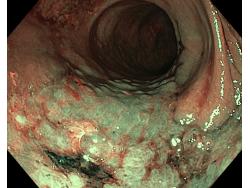

Nowotwory przewodu pokarmowego